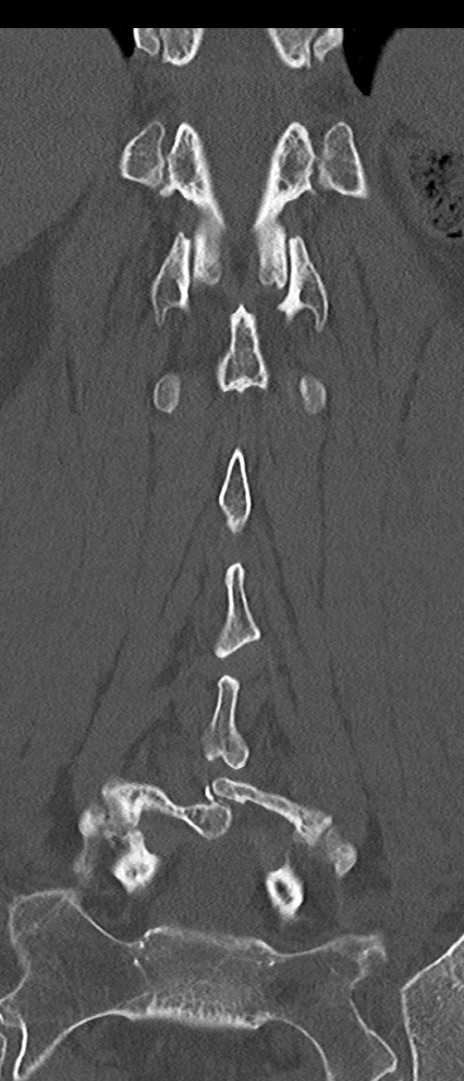

【整形】TIPS症例4 腰椎CT(冠状断像)

腰椎CT

矢状断像